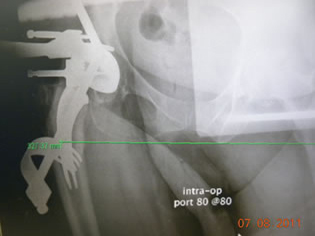

|

| X-ray confirmed our impression that we could go up in size of the stem and neck length. The offset appeared to be good with a neutral modular neck and 0 head with a 36 mm poly insert. |

The trial stem extractor works well and functions as a reminder of how to extract the final stem if it ever becomes necessary. |